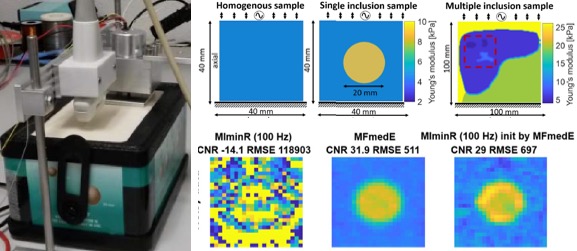

[2018] Corin F. Otesteanu, Sergio J. Sanabria, and Orcun Goksel:

"Robust Reconstruction of Elasticity Using Ultrasound Imaging and Multi-frequency Excitations",

IEEE Trans Medical Imaging 37(11):2502-2513, Nov 2018.

[2018] Corin F. Otesteanu, Sergio J. Sanabria, and Orcun Goksel:

"Robust Reconstruction of Elasticity Using Ultrasound Imaging and Multi-frequency Excitations",

IEEE Trans Medical Imaging 37(11):2502-2513, Nov 2018.

@article{Otesteanu_robust_18,

author = {Corin F Otesteanu and Sergio J Sanabria and Orcun Goksel},

title = {Robust Reconstruction of Elasticity Using Ultrasound Imaging and Multi-frequency Excitations},

journal = {IEEE Trans Medical Imaging},

year = {2018},

volume = {37},

number = {11},

pages = {2502-2513},

doi = {10.1109/TMI.2018.2837390}

}

[2018] Corin F. Otesteanu, Valeriy Vishnevskiy, and Orcun Goksel:

"FEM Based Elasticity Reconstruction Using Ultrasound For Imaging Tissue Ablation",

Int J Computer Assisted Radiology and Surgery 13(6):885-894, Jun 2018.

[2018] Corin F. Otesteanu, Valeriy Vishnevskiy, and Orcun Goksel:

"FEM Based Elasticity Reconstruction Using Ultrasound For Imaging Tissue Ablation",

Int J Computer Assisted Radiology and Surgery 13(6):885-894, Jun 2018.

@article{Otesteanu_fem_18,

author = {Corin F Otesteanu and Valeriy Vishnevskiy and Orcun Goksel},

title = {FEM Based Elasticity Reconstruction Using Ultrasound For Imaging Tissue Ablation},

journal = {Int J Computer Assisted Radiology and Surgery},

year = {2018},

volume = {13},

number = {6},

pages = {885-894},

doi = {10.1007/s11548-018-1714-x}

}